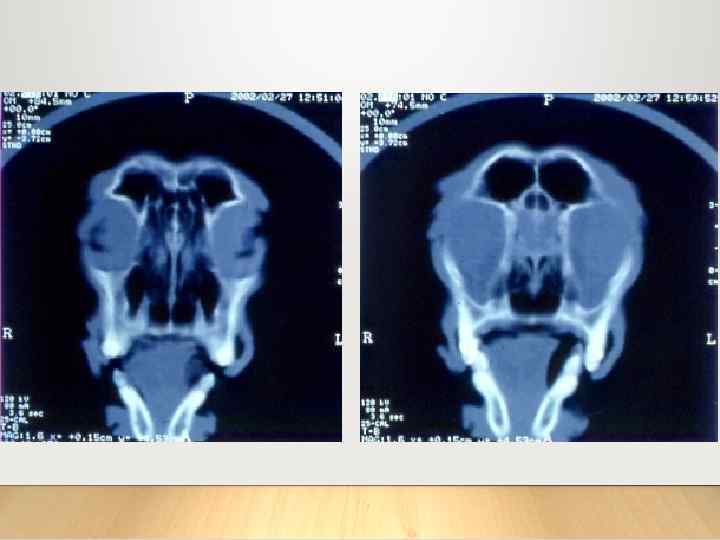

Компьютерная томография